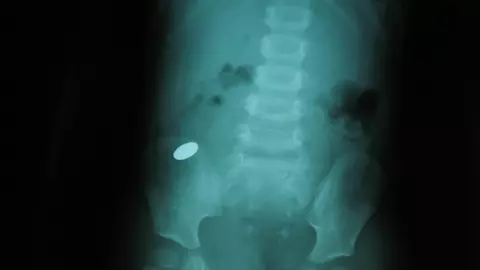

Copiii sunt curiosi din fire, insa uneori asta ii poate pune in mare pericol. Un baiat de 12 ani a aflat asta pe propria piele, dupa ce a inghitit accidental nici mai mult, nici mai putin de patru magneti. Freddie, un baiat de 12 ani din Anglia, se juca si incerca sa testeze forta a